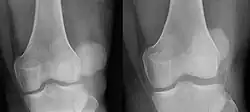

In jedem Fall muss – falls dies nicht von selbst geschehen ist – die Kniescheibe eingerenkt werden. Hierbei sollte unter Anleitung des Arztes oder eines erfahrenen Sporttrainers das Knie langsam und vorsichtig wieder gestreckt werden, wobei die Kniescheibe fest mit der Hand geführt wird, damit sie nicht unvermittelt überspringt. Wenn die Kniescheibe vorsichtig in die Ausgangsposition geführt wird, kann diese ohne Begleitverletzung der Gelenkflächen wieder reponiert werden. Dabei sollte es nicht zu einem heftigen Einschnappen kommen, was einen Knorpelschaden verursachen kann. Der Betroffene merkt nach der Reposition eine deutliche Schmerzlinderung. Nach der Reposition sollte das Knie geröntgt werden und eine Kernspintomographie erfolgen, um die richtige Lage der Kniescheibe zu kontrollieren und um Begleitverletzungen auszuschließen.